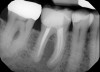

CBCT technology can be used for 3D location of jaw pathologies, to assess impacted teeth and supernumerary teeth, to assess the relation of the teeth to vital structures, to assess changes in the cortical and trabecular bone in cases of bisphosphonate-associated necrosis of the jaws, and to evaluate bone grafts. CBCT is also used to investigate the pathologies related to paranasal sinuses and to assess obstructive sleep apnea. CBCT technology also can be used to access endodontic lesions, root fractures, and resorption lesions (Figure 3 and Figure 4).10

Fig 3. A traditional periapical radiograph of a symptomatic endodon-

tically treated first molar.

Figure 3

Fig 4. CBCT image showing an intraradic-

ular abscess of the endodontically treated first molar in Fig 3.

Figure 4